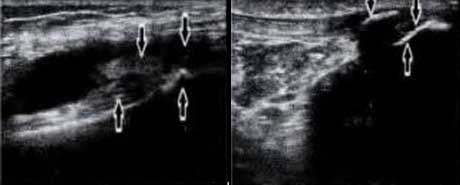

三、准确检测骨质细微病变,辅助评估骨质受损程度

肌骨超声不仅能够较好地显示关节及周围软组织的病理改变,还能清晰地显示骨皮质表面附着端的异常和骨性水肿,检测到骨和软骨表面的细微病变、小的骨质缺损。此外,在超声影像下,肌腱所附着的关节处骨皮质破坏、骨质糜烂,“虫蚀样”改变,邻近骨质的反应性硬化及绒毛样改变,关节软骨与滑膜交界处骨轮廓“火山口”样缺损,软骨透明度的丢失和软组织界面完整性的丢失情况都均能清晰显示。通过研究证实,超声对肌腱及其附着处骨皮质的观察,有利于更准确的评估AS患者外周关节的骨质破坏程度,进而判断病情严重程度。

软骨损伤

AS患者骨皮质中断、不连续,可见到游离骨片

骨质钙化受、改变

肌腱附着处滑囊内伴积液,呈“虫蚀样”改变、见钙化灶